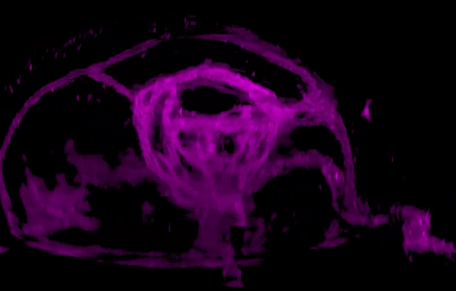

研究人員發(fā)現(xiàn),視網(wǎng)膜干細(xì)胞只能由視泡中間上皮細(xì)胞中一群雙潛能細(xì)胞產(chǎn)生,這群雙潛能細(xì)胞產(chǎn)生視網(wǎng)膜干細(xì)胞的同時產(chǎn)生視網(wǎng)膜色素細(xì)胞。為深入研究視網(wǎng)膜干細(xì)胞發(fā)育的分子機(jī)制提供了細(xì)胞譜系基礎(chǔ),為最終理解視網(wǎng)膜干細(xì)胞的產(chǎn)生和維持機(jī)制提供可能。